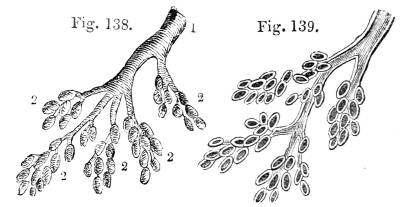

Fig. CXXXVIII.—

View of the Bronchial Tubes terminating

in Air vesicles.

Fig. 138.Fig. 139.

External view.—1. Bronchial tube. 2. Air vesicles. Fig.

139. The same laid open.

present a clustered appearance, not unlike

clusters of currants attached to their stem (fig.

CXXXVIII. 2).